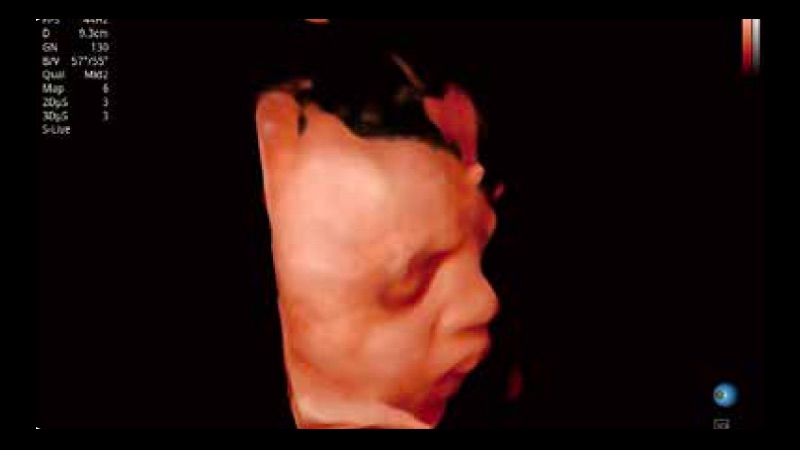

開(kāi)立醫(yī)療通過(guò)不斷的技術(shù)創(chuàng)新,為大眾的生命健康提供持續(xù)關(guān)愛(ài)。P12 Plus采用全新一代超聲成像平臺(tái),新平臺(tái)旨在將真實(shí)還原組織解剖結(jié)構(gòu)作為首要目標(biāo)。平臺(tái)采用全新集成化硬件模塊,搭載新一代芯片,系統(tǒng)性能得到大幅提升,為您的診斷提供了豐富的臨床信息。優(yōu)異的圖像表現(xiàn),豐富的探頭配置,全面的應(yīng)用功能,為您日常診斷提供了可靠的助手。